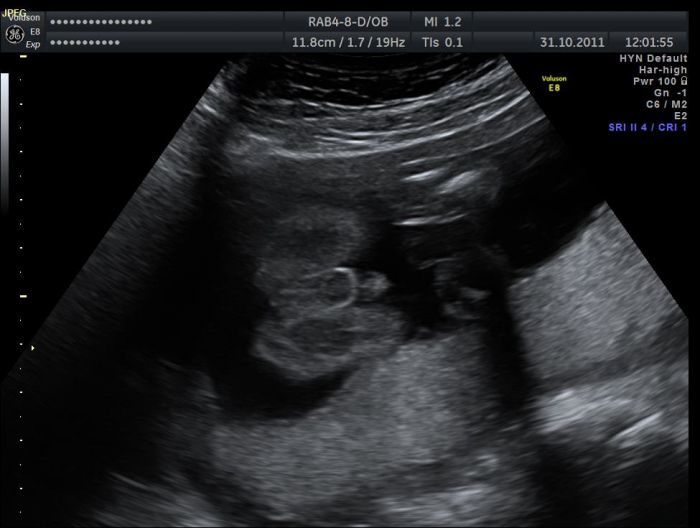

20+5 Ahoj holky, posílám ještě fotečky ze včerejšího UZ...celý mimi se už bohužel na fotku nevejde, tak máme aspoň profil...:) a ten druhý obrázek - to je prosím kubíkovo pohlaví, prý na 99 % kluk - no je pravda, že obrázek mluví za vše...:)